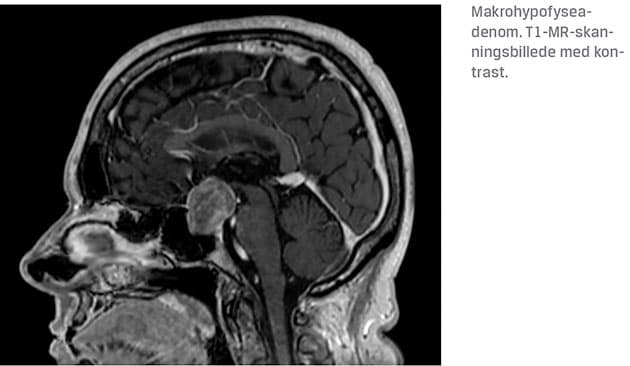

HA inddeles i mikro (< 10 mm) og makro (≥ 10 mm) adenomer samt efter evt. hormonaktivitet i klinisk nonsecernerende og secernerende HA. Omkring 50% af de påviste hypofysenære læsioner er mikroadenomer [5]]. Makroadenomer er som oftest symptomatiske pga. tryksymptomer, som medfører: 1) påvirkning af synsfunktionen og 2) hypofyseinsufficiens (evt. som følge af stilktryk) (Tabel 1). Synsudfaldene opstår ofte først i øvre temporale kvadrant [8], men der er stor variation i påvirkning af synet, hvor eneste fund kan være en oftalmoplegi (øjenmuskelparese). I sjældnere tilfælde kan HA, betinget af tryk på den omkringliggende hjerne, forårsage hydrocephalus, fokale neurologiske udfald og epilepsi. Ved akut udviklet synstab eller komplet blindhed skal man have mistanke om pituitær apopleksi.